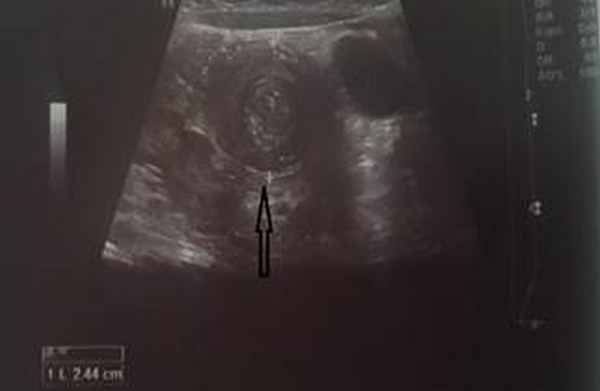

На рисунках 2 и 3 отображена ультразвуковая картина кишечной инвагинации.

Рис. 2. Симптом «мишени»

В момент УЗ-исследования врач может определить один из симптомов:

- симптом мишени (за счёт внедрения одной кишки в другую инвагинат на срезе выглядит как мишень);

- симптом "почки с завоздушенным центром".